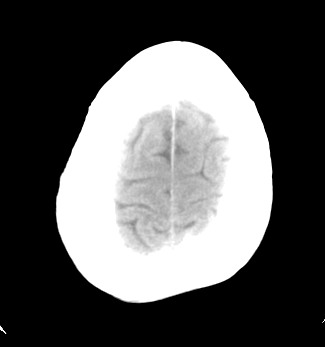

标题: CT17787:头ct,请帮忙看看右顶部有无异常 [打印本页]

男,58岁,偶有头疼

未见明显异常。右顶部低密度影为深入的脑沟。

增宽的脑沟!无异常!

是宽大的脑沟,局部不象有萎缩现象

增宽的脑沟

诊断依据:

低密度影周围脑组织边缘均有一层脑灰质覆盖。

正常啊,是对右顶增宽脑沟有疑问吗